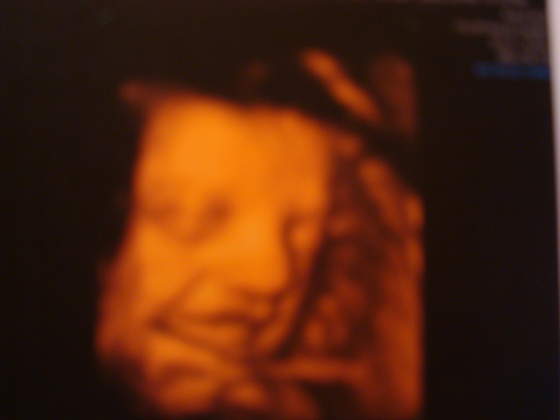

a oto mój słodziak:

nasz Mateusz waży 3010g w 34tyg i 1 dzień![]()